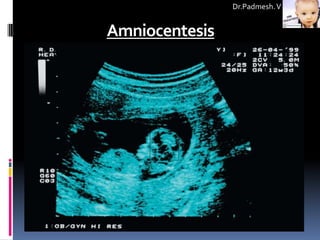

a) USG:

 Noninvasive procedure for imaging fetal anatomy.

 Harmless to both the fetus and the mother.

 Anatomical lesions, including some

genitourinary, gastrointestinal, skeletal, and central nervous system

abnormalities and congenital cardiopathies, can be visualized by

ultrasound between 16-20 weeks' gestation.

 Ultrasound also is used to guide invasive sampling, such as

amniocentesis, CVS, cordocentesis, and various fetal biopsies.

 Amniocentesis

 Amniocentesis is an invasive, well-established, safe, reliable, and accurate

procedure performed between 14-20 weeks of pregnancy.

 It is performed under ultrasound guidance.

 A 22-gauge needle is passed through the mother's lower abdomen into the

amniotic cavity inside the uterus, and 10-20 mL of amniotic fluid that contains

cells from amnion, fetal skin, fetal lungs, and urinary tract epithelium are

collected.

Amniocentesis